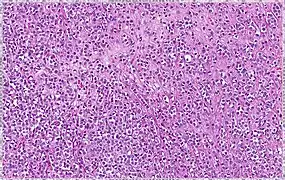

| Solid | 10% | Sheets of classical-appearing cells with little intervening stroma | |

| Pleomorphic | Classical-appearing but with pleomorphic cells. It may include signet-ring cells, or plasmacytoid cells (pictured) which have abundant cytoplasm and eccentric nuclei. | ![]() |